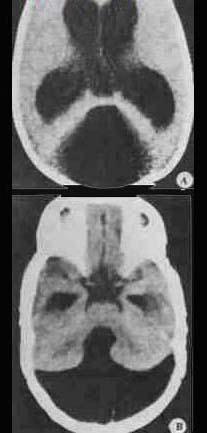

(见图)所示,最可能诊断为()A.中脑导水管狭窄B.脑出血C.Dandy-Walker畸形D.交通性脑积水E.以上均不对

问题 (见图)所示,最可能诊断为()

选项 A.中脑导水管狭窄 B.脑出血 C.Dandy-Walker畸形 D.交通性脑积水 E.以上均不对

答案 C